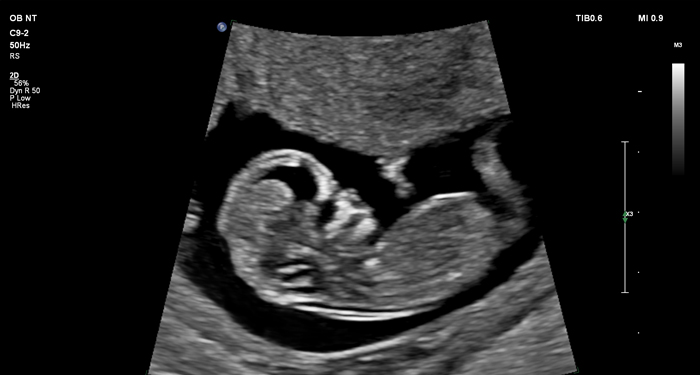

At the touch of a button, the new MaxVue high-definition display brings extraordinary visualisation of anatomy with 1,179,648 additional image pixels compared to a standard 4:3 display format mode. MaxVue enhances ultrasound viewing during interventional procedures and provides 38% more viewing area to optimise the display of dual, side/side, biplane, and scrolling imaging modes.